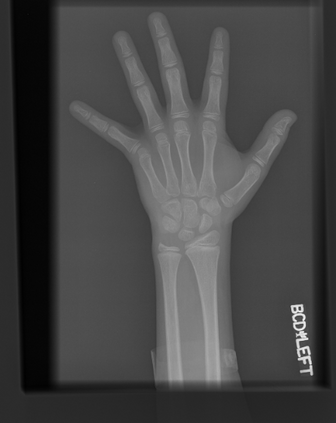

Deep neural networks are increasingly being used for the analysis of medical images. However, most works neglect the uncertainty in the model's prediction. We propose an uncertainty-aware deep kernel learning model which permits the estimation of the uncertainty in the prediction by a pipeline of a Convolutional Neural Network and a sparse Gaussian Process. Furthermore, we adapt different pre-training methods to investigate their impacts on the proposed model. We apply our approach to Bone Age Prediction and Lesion Localization. In most cases, the proposed model shows better performance compared to common architectures. More importantly, our model expresses systematically higher confidence in more accurate predictions and less confidence in less accurate ones. Our model can also be used to detect challenging and controversial test samples. Compared to related methods such as Monte-Carlo Dropout, our approach derives the uncertainty information in a purely analytical fashion and is thus computationally more efficient.